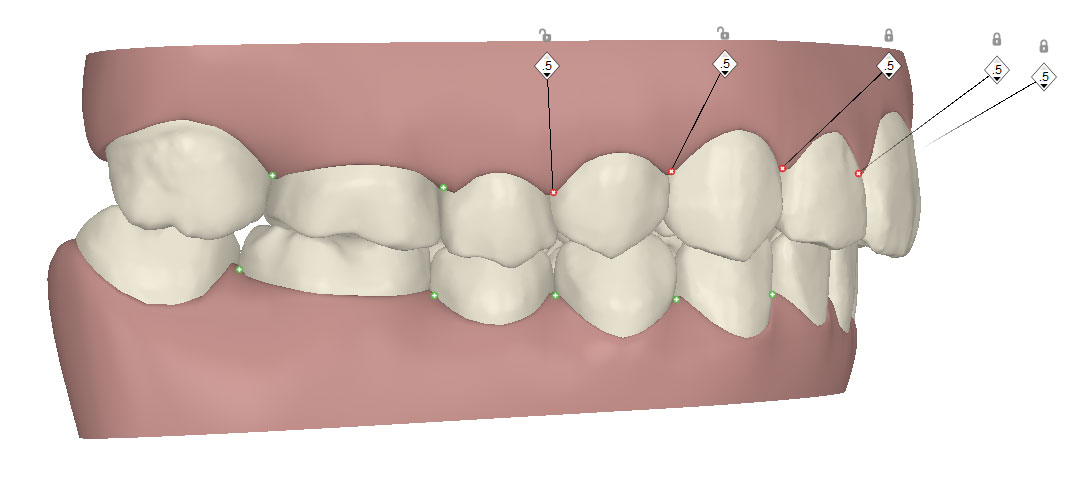

コンピューターを使って作製した透明なマウスピース型の矯正装置(アライナー)を段階的につけ替えていき、それにより歯列を矯正し、歯並びへと改善します。はじめに 治療開始から終了までのアライナーができあがってきます。マウスピース型矯正装置(インビザライン)の最大の特徴として「クリンチェック」というソフトがあります。3D のコンピュータ シュミレーション画像で、治療開始から完了までを目で見て確認することができます。

マウスピース型矯正装置(インビザライン)治療においては、クリンチェックというシミュレーションソフトを活用しております。

このクリンチェックの魅力は、治療前の現在の歯並びから治療後の歯並びを視覚化して患者様にご説明できる点にあります。

また、抜歯・非抜歯、全体矯正・部分矯正などそれぞれの治療パターンをシミュレーションすることが可能です。

| ライトプラン 隣接面削合なし |

| ライトプラン 隣接面削合あり |

| フルプラン 隣接面削合あり |